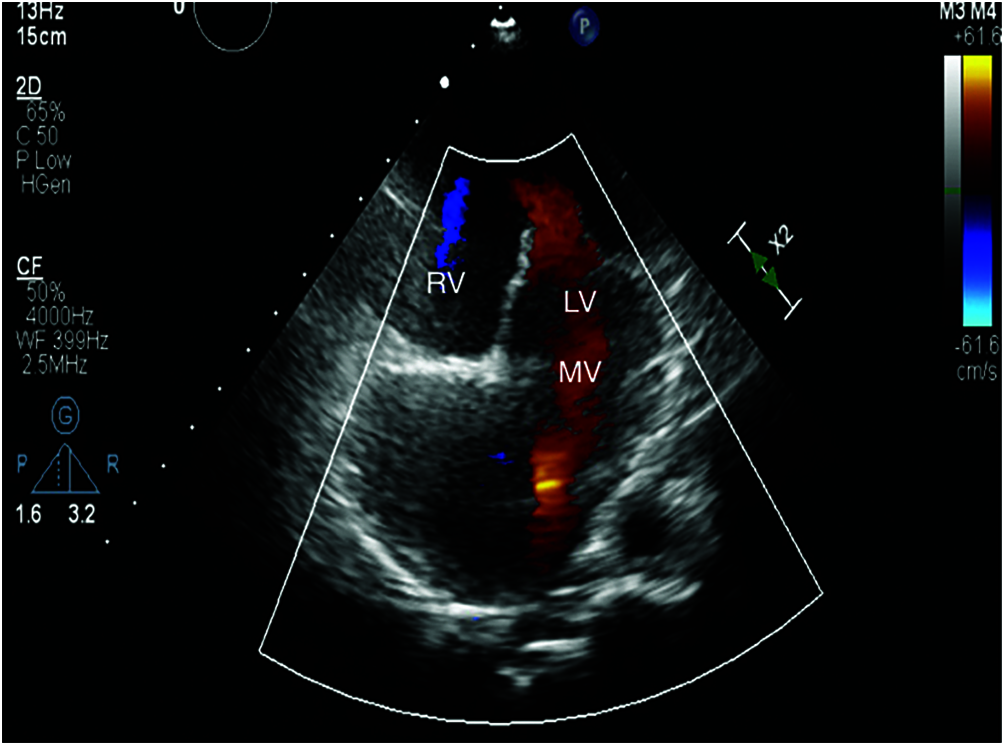

Full ECG gated echocardiographic study using echocardiography machine with phased array transducer of suitable frequency to perform sequential segmental analysis (Figs. 1 and 2).

Figure 1: Apical 4 chamber view showing tricuspid atresia in patient number 2 (MV: mitral valve, LV: left ventricle, RV: right ventricle)